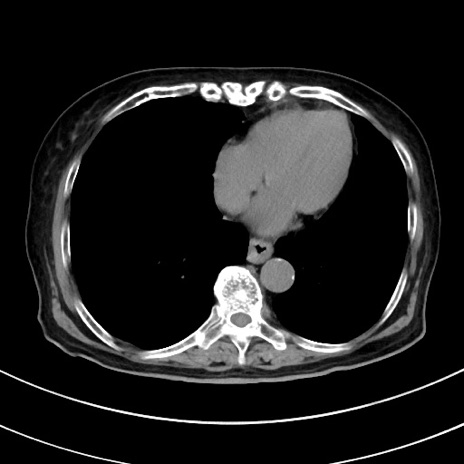

症例33(横断像)

【症例】70歳代 女性

【主訴】心窩部痛

【現病歴】延髄病変の精査・加療にて神経内科入院中。本日より心窩部痛あり。

【身体所見】右下腹部を中心に圧痛と反跳痛あり。